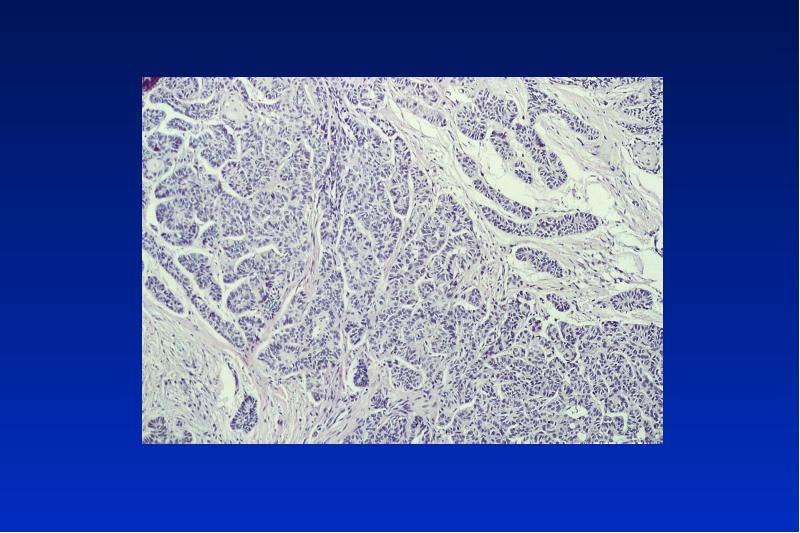

- 38. Ameloblastom solid intraössär/ peripher/unizystisch/ maligen benigner, lokal aggressiv wachsender Tumor

- 50. Kalzifizierender epithelialer odontogener Tumor (Pindborg Tumor) benigner lokal invasiver